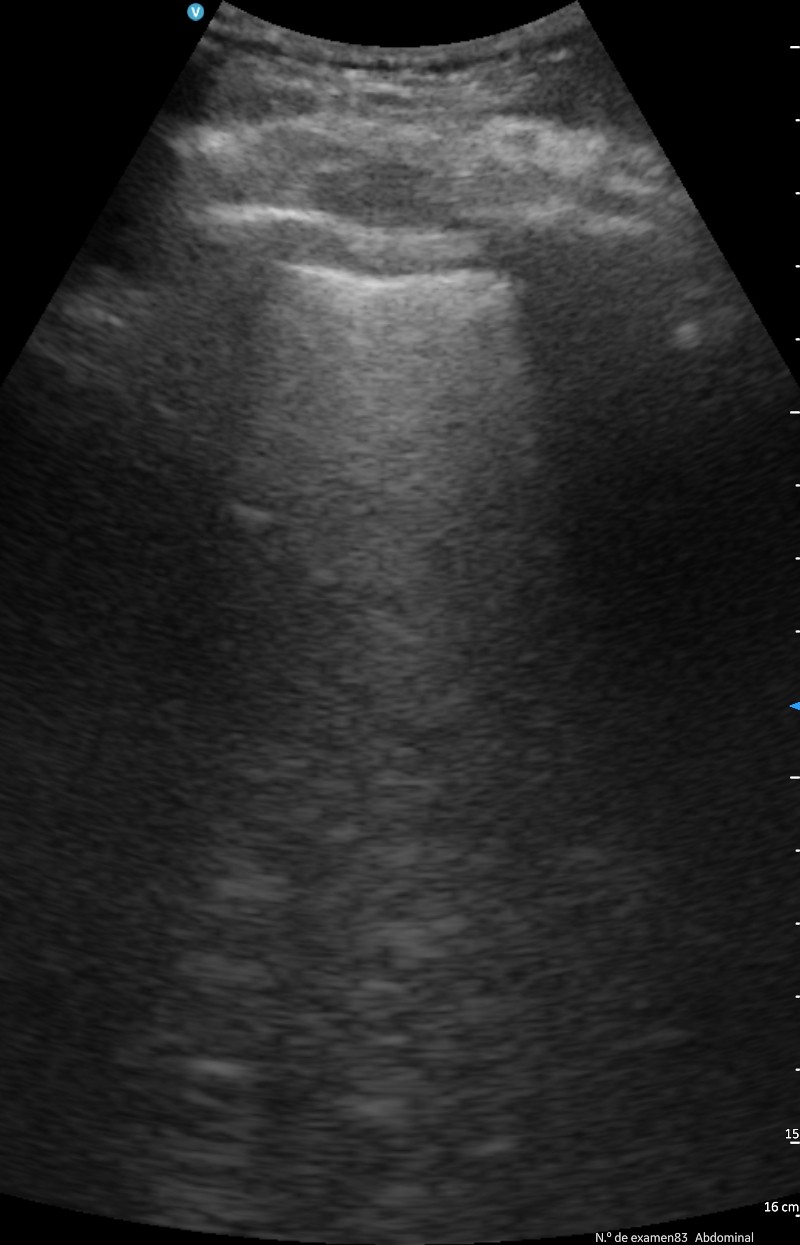

El principal uso ha sido para controlar la evolución de las insuficiencias cardíacas, controlando las líneas B, los derrames pleurales, colapso de la vena cava inferior, etc., en menores casos se ha hecho una ecocardioscopia para estimar la FEVI.

También ha sido útil en las insuficiencias respiratorias por COVID-19 o por neumonías para controlar las consolidaciones y los derrames pleurales.